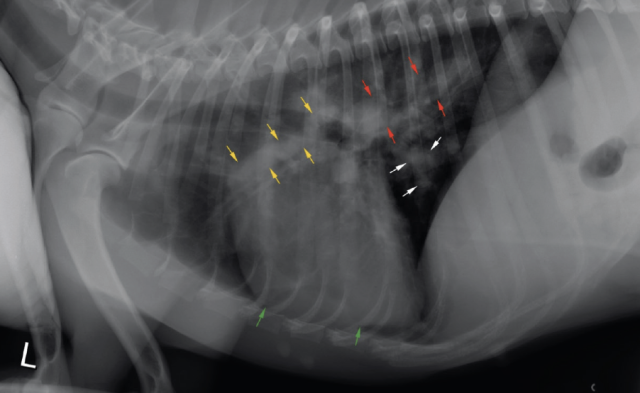

Thoracic radiographs revealed enlargement of the pulmonary arteries, mild to moderate right ventricular enlargement and a moderate diffuse, unstructured interstitial pattern with patchy alveolar areas within the right cranial and middle lung lobes (see Figures 1 and 2). Echocardiography revealed right atrial enlargement with bulging of the interatrial septum to the left, mild subjective enlargement of the right ventricle and mild to moderate central pulmonic regurgitation with a mildly elevated velocity (2.8m/s; reference value <2.2m/s). The pulmonary artery was mildly enlarged and contained multiple mobile, tortuous linear hyperechoic structures, likely to reflect the presence of adult worms (see Figure 3). The laboratory test results in combination with the imaging findings were consistent with a diagnosis of canine dirofilariasis.

When re-presented, the dog was hypoxemic and required oxygen therapy. Haematology, biochemistry and standard coagulation times were unremarkable, and the antigen test for D. immitis was now negative. Thoracic radiographs revealed right-sided cardiomegaly, a worsening of the alveolar lung pattern, consistent with haemorrhage or pneumonia, and a severe widening of the right cranial lobar pulmonary artery. Echocardiography confirmed enlargement of the right side of the heart and showed severe tricuspid insufficiency with increased regurgitation velocity (3.95m/s; reference value <2.8m/s), suggesting severe pulmonary hypertension, likely to be the result of the heavy worm burden identified in the right branch of the pulmonary artery. The dog remained hospitalised for two days, initially with oxygen supplementation. Glucocorticoid treatment was re-commenced, initially with dexamethasone, at 0.1mg/kg intravenously, once daily (SID); then, oral prednisolone at 0.5 mg/kg SID, as well as doxycycline at 10mg/kg, orally SID. Given the presence of pulmonary hypertension, as evidenced by the abnormal increase in tricuspid regurgitation velocity in the absence of pulmonic stenosis, the dog was also started on sildenafil citrate at 1.25mg/kg orally, three times daily (TID).